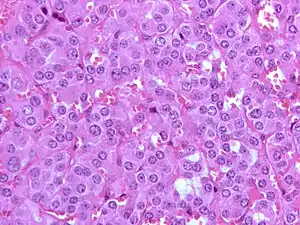

Feocromocitom

Feocromocitomul reprezintă o tumoare endocrină a medulosuprarenalei (celulele cromafine), fiind caracterizat prin secreția masivă de catecolamine (în special noradrenalină). Feocromocitomul primar extrasuprarenalian (ganglioni simpatici din sistemul nervos vegetativ) este cunoscut ca paragangliom (aproximativ 10%-15% din cazuri de feocromocitom). Numai 10% din tumorile medulosuprarenaliene sunt maligne.